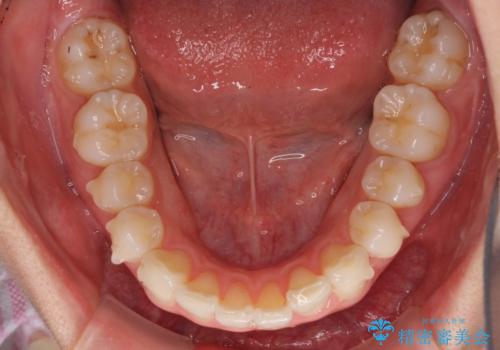

- 上下前歯の叢生を気にして来院された患者様です。

以前矯正をした後戻りということで、歯列不正はそれほど大きくなかったため、インビザライン・ライトを用いて矯正治療を行うこととしました。

前歯のデコボコが残っており、シミュレーション通りに動いていない部分がありましたが、再矯正であることやご本人の満足いくところまでデコボコが改善されたとのことで、治療を終了することとしました。